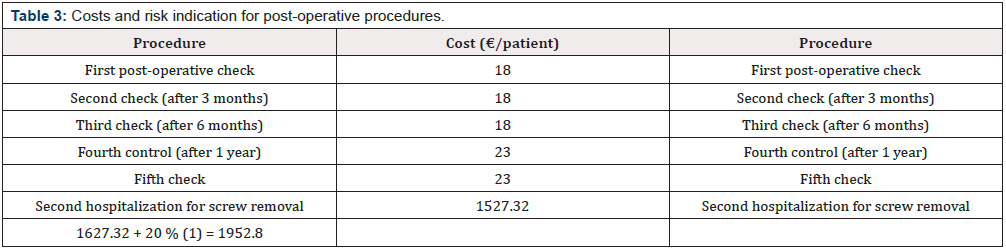

Post-Operative Stage

For a correct post-operative course, a sequence of 5 orthopedic check-ups are required. These are carried out with a time interval of about 3 months from each other. If after the first 4 visits no problems occurs, during the last visit the removal of the screws will take place, a procedure that requires a small intervention in Day Surgery. The cost of the post-operative stage is listed in (Table 3). (Table 4) summarize the traditional methodology emphasizing the main issues that have been identified during the analysis of the traditional technique.

Innovative Procedure Profits